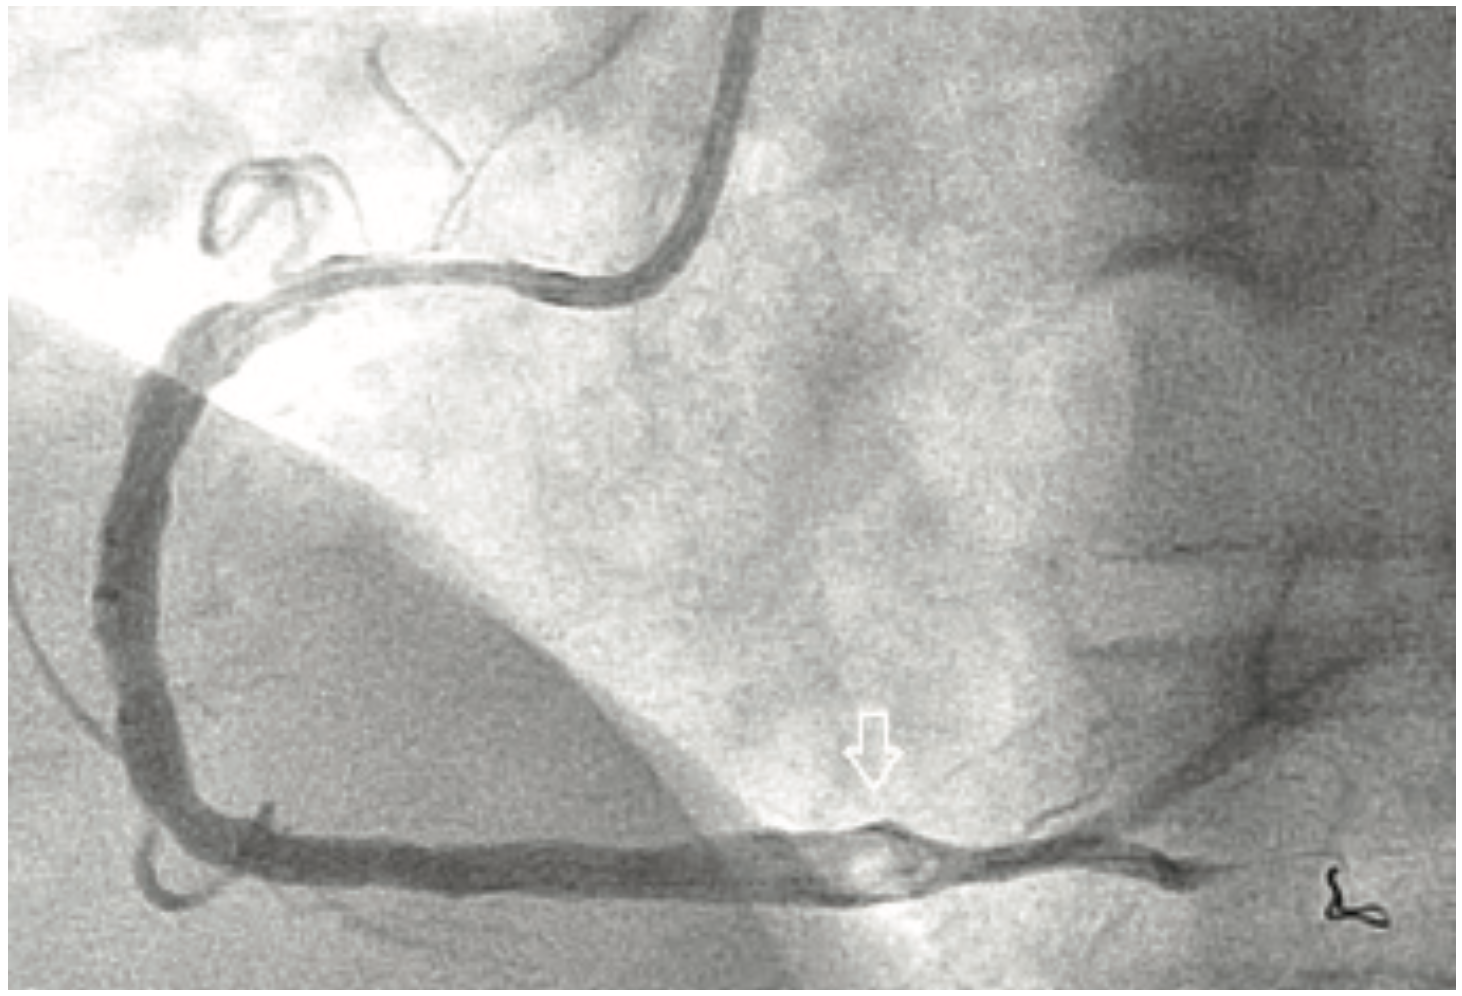

A 47-year-old male without prior cardiac history presented with an inferior ST-elevation myocardial infarction (STEMI) and received thrombolytics at an outside facility. Upon transfer to our facility, he was taken immediately to the cath lab due to continued angina and ST elevations. Angiography revealed a large distal RCA thrombus proximal to the bifurcation with TIMI-2 flow (Figure 3). Through a 6 Fr Judkins right (JR) 4.0 guide catheter and a 6 Fr GuideLiner, a Runthrough NS coronary wire (Terumo) was advanced to the distal RCA branch. The GuideLiner was carefully advanced to the distal RCA at the site of the thrombus and aspiration was attempted using a 50 cc syringe, but with only partial success. A stent (Xience 4.0 x 18 mm [Abbott Vascular]) was deployed at 20 atm proximal to the RCA bifurcation, with full expansion, but persistent thrombus in the stented segment. The GuideLiner once again was carefully advanced to the thrombus and after second aspiration attempt, there was complete clearance of the thrombus (Figure 4). TIMI-3 flow with no evidence of distal embolization was noted. The patient was started on optimal medical therapy, including continuation of a GP IIb/IIIa inhibitor, and was discharged 3 days later without any complications.